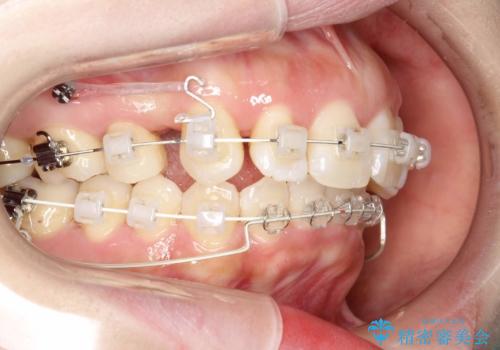

抜歯をして前歯を下げ、ガタつきを取り除く ワイヤー矯正

- 矯正装置

- 審美装置

- 上顎両側第1小臼歯、下顎左側第2小臼歯の3本を抜歯、ラビアルのワイヤー矯正を計画した。

ワイヤーを用いることで、矯正中に生じる様々な問題にその場で対処することができます。